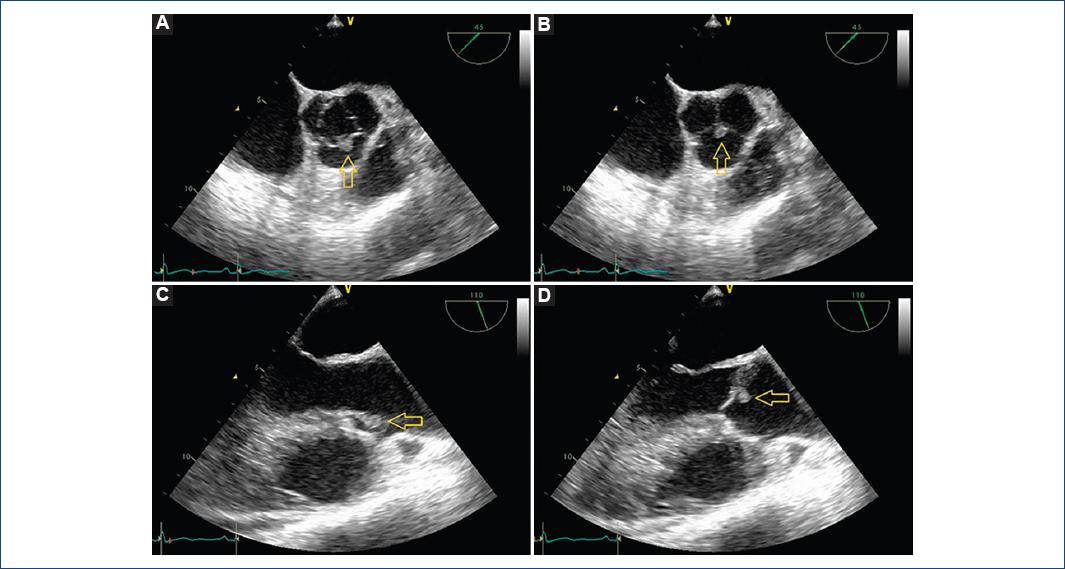

Se iniciaron tratamiento anticoagulante y estudio etiológico. La ecocardiografía transtorácica objetivó una tumoración de pequeño tamaño en el velo coronariano derecho, sobre válvula aórtica trivalva, sin disfunción valvular y sin otras alteraciones. La ecocardiografía transesofágica confirmó la tumoración vibrátil en la cara aórtica del velo coronariano derecho, de 0.5 cm, sugestiva de fibroelastoma papilar, sin flujos patológicos (Fig. 1). Se descartaron comunicación interauricular y trombos en la orejuela izquierda. Pasada la fase aguda del ictus, se realizó resonancia magnética cerebral, sin evidencia de complicación hemorrágica, con afectación del córtex motor extensa. Residualmente, presentaba hemiparesia derecha y disfasia motora. Se completó el estudio con coronariografía, que descartó lesiones, y se decidió realizar cirugía.

Figura 1 Ecocardiografía transesofágica preoperatoria que muestra la tumoración (flecha). A: corte transversal basal, apertura de válvula aórtica. B: válvula aórtica cerrada. C: corte medio transversal de cinco cámaras, válvula aórtica abierta. D: válvula aórtica cerrada.